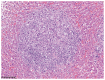

Prototheca osteomyelitis in a dog

Canine systemic protothecosis is an uncommon disease caused by Prototheca spp., which are saprophytic algae occurring ubiquitously in nature. Infection occurs most commonly in immunocompromised animals. Most infected dogs have chronic large-bowel diarrhea, ocular lesions, neurologic deficits, or a combination thereof, but various tissues can be affected. This case highlights a unique presentation of protothecosis in a dog, in which lameness resulting from osteomyelitis was the predominant clinical sign. Key clinical message: Although osteomyelitis is an atypical manifestation, protothecosis can be a differential diagnosis for an aggressive bony lesion and is particularly worthy of consideration in immunocompromised dogs.